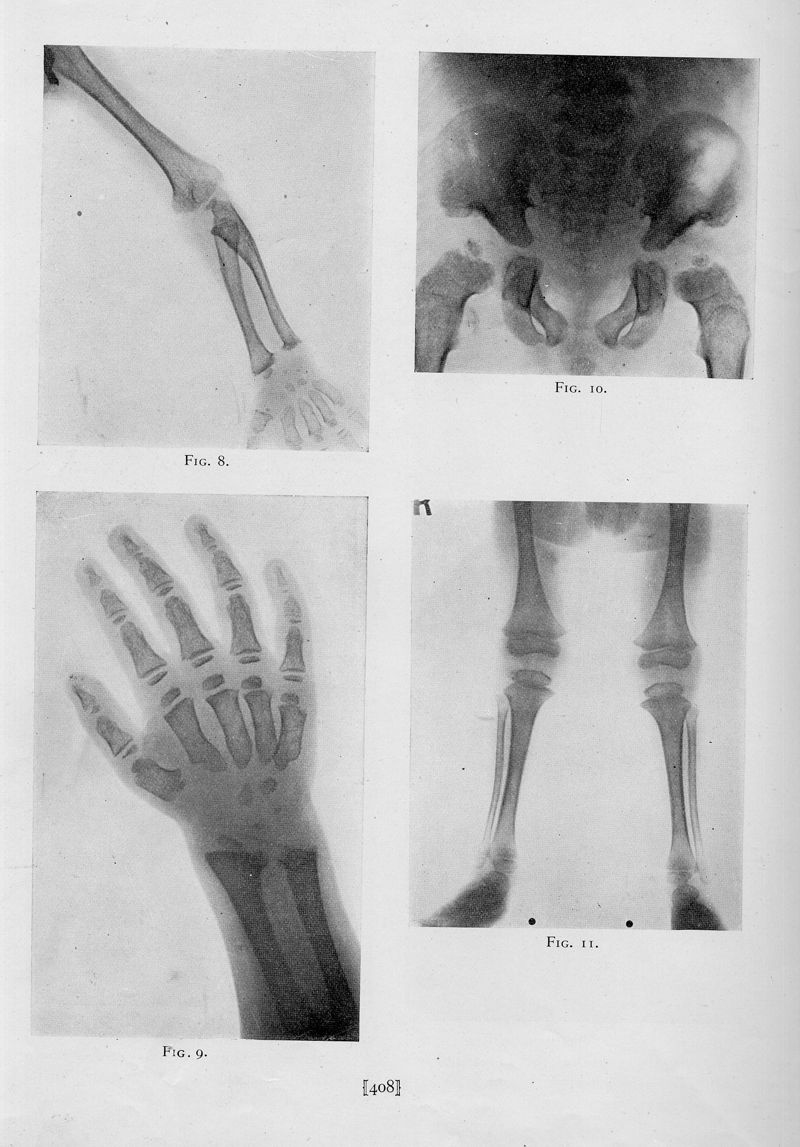

Chondro-osteo-dystrophy. Roentgenographic and clinical features of a child with dislocation of vertebrae

In : [The] American journal of surgery, 1929, Vol. 7, pp. 404-10